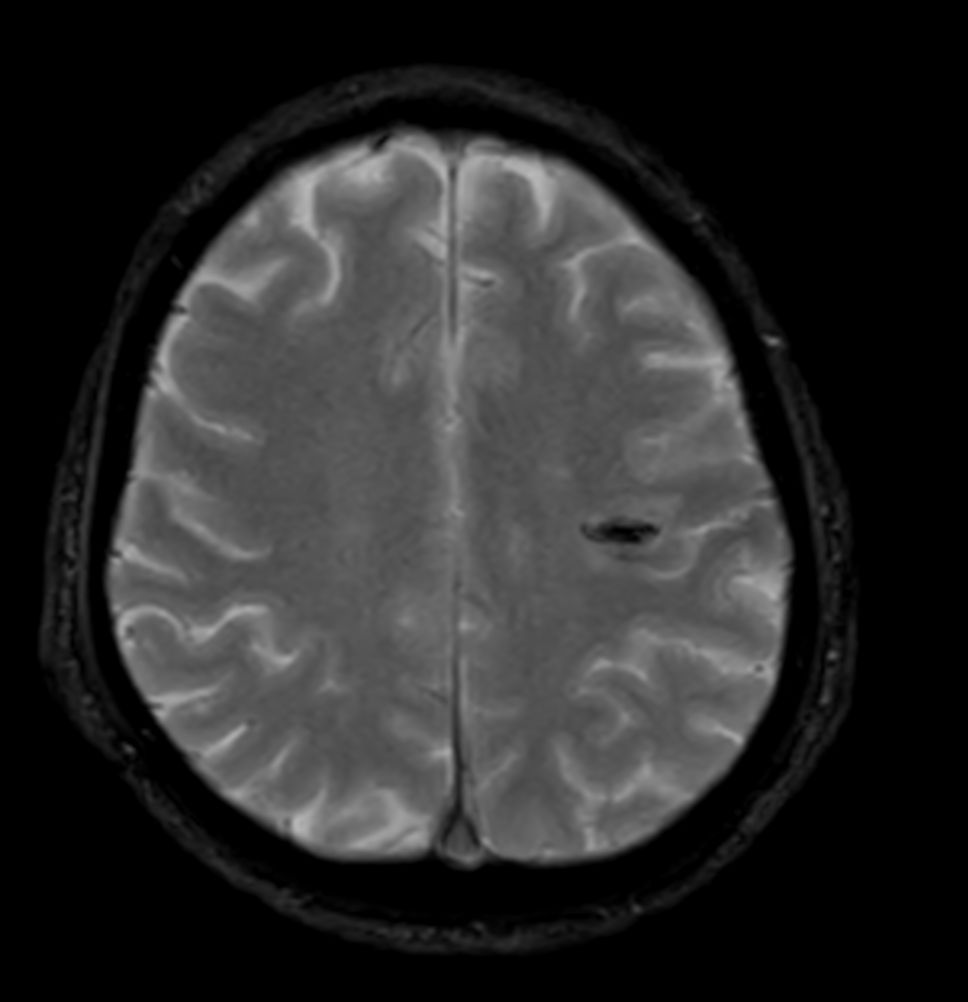

Patient with a small brain infarction. Compressed SENSE acceleration is used to speed up sequences while maintaining equal image quality. Three different diffusion methods are included; A fast 52 secs DWI EPI sequence, a high resolution DWI EPI sequence and a TSE based DWI sequence. A SWIp sequence is included offering high resolution 3D susceptibility weighted imaging to enhance contrast for deoxygenated (venous) blood or calcium deposits. 3D APT sequence is included providing contrast-free brain imaging, addressing the need for more confident diagnosis in brain neuro oncology by using the presence of endogenous cellular proteins to produce an MR signal. And a large FOV TOF MR Angiography sequence is included to check on brain vascular anatomy.

Axial T2w TSE - Compressed SENSE

Axial T2w FLAIR - Compressed SENSE